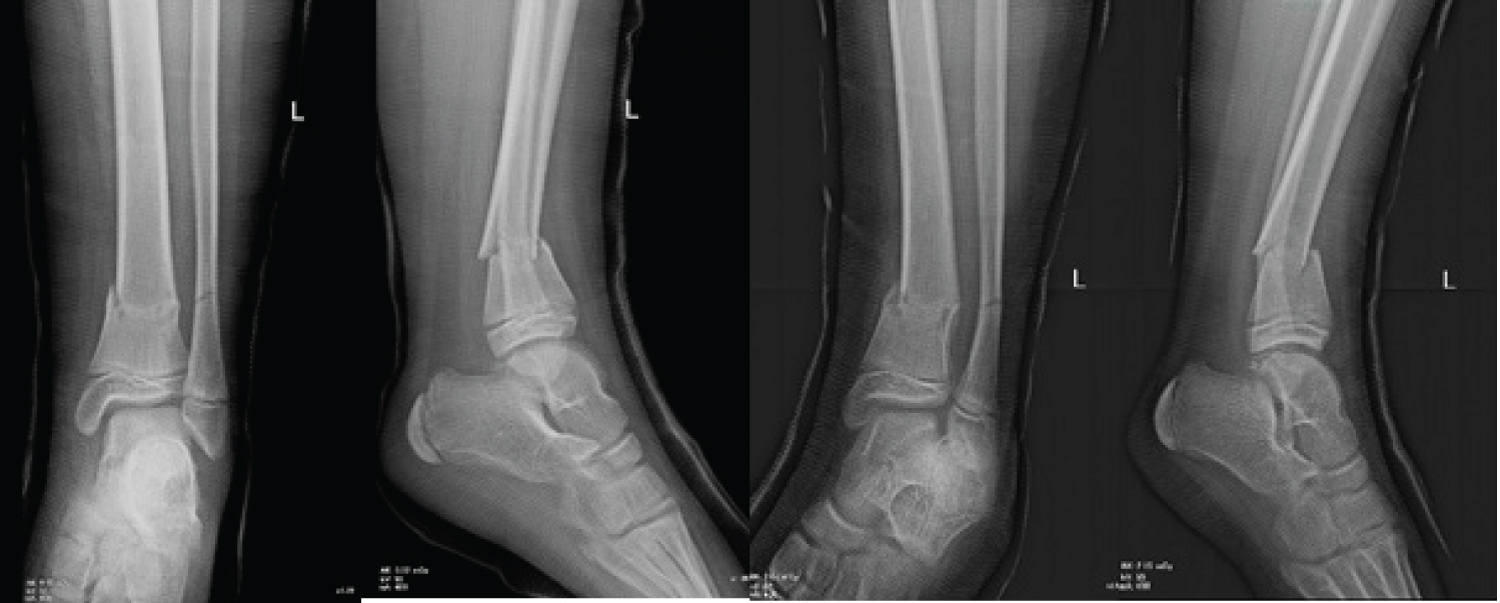

The therapeutic strategy was going toward a conservative treatment with a non-weight bearing long leg cast for 3-4 weeks, then switching to a short leg cast for another 3-4 weeks. So, a long leg cast was done with 20 degrees of knee flexion and a plantar flexion of the foot to avoid secondary displacement. A control radiograph after casting revealed an increase in the recurvatum deformity that reached 9 degrees, still within the tolerable ranges (Figure 2).

Figure 2: AP and lateral radiographs showing the increased but tolerable fracture displacement after casting. View Figure 2

Follow up radiographs were performed during the first two weeks at day 7 and day 14, and the displacement had clearly increased. We had at day 14 a recurvatum of 19 degrees and a varus of 11 degrees (Figure 3). Therefore, at the present situation, surgical intervention was mandatory to restore the anatomy.

Figure 3: AP and lateral radiographs showing displacement exaggeration two weeks after casting, (A) at day 7 and (B) at day 14. View Figure 3